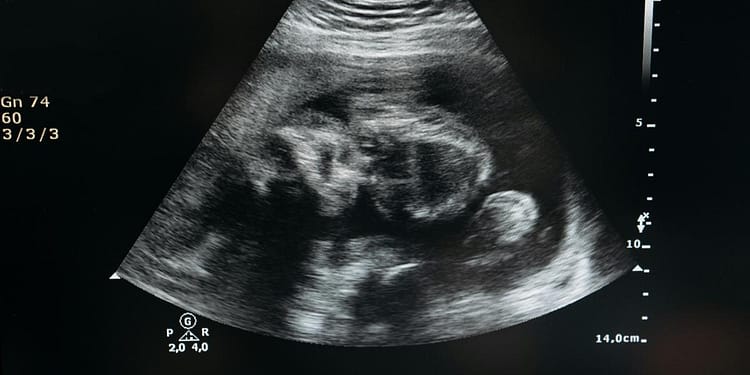

Un fenomen extrem de rar în obstetrică, lithopedionul sau „bebelușul de piatră” reprezintă calcificarea unui făt decedat care rămâne în organismul mamei, fără a fi eliminat.

Această condiție apare în urma unei sarcini ectopice abdominale, atunci când fătul moare, dar este prea mare pentru a fi reabsorbit de corpul mamei. Pentru a preveni infecțiile, organismul mamei învelește fătul într-un strat de calciu, transformându-l într-o masă solidă asemănătoare pietrei.

Lithopedionul se formează atunci când un făt moare în urma unei sarcini ectopice abdominale și este prea mare pentru a fi reabsorbit de corpul mamei. În loc să fie eliminat, fătul este învelit într-un strat de calciu, protejând astfel organismul mamei de infecții. Această calcifiere poate dura zeci de ani, iar femeile afectate pot rămâne asimptomatice sau pot prezenta simptome minore.